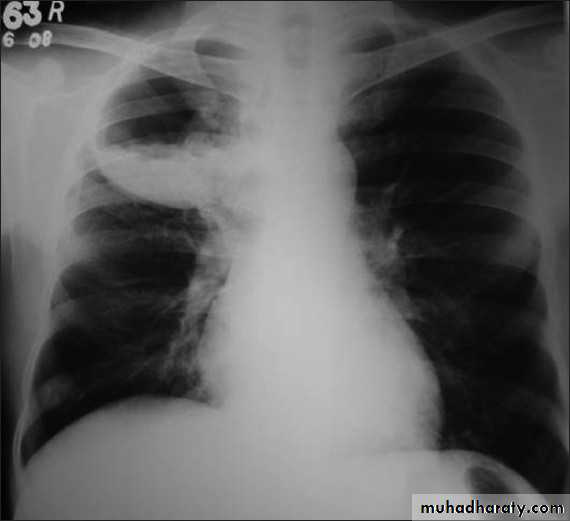

Pneumothorax

Pneumothorax refers to the presence of gas (air) in the pleural space. When this collection of gas is constantly enlarging with resulting compression of mediastinal structures it can be life-threatening and is known as a tension pneumothoraxIt is useful to divide pneumo thoraces into three categories :

primary spontaneous: no underlying lung disease marfan syndrum , Elher danus syndrome alpha-1 antitrypsin deficiency

secondary spontaneous: underlying lung disease is present

iatrogenic/traumatic

Radiographic features

Chest radiographA pneumothorax is, when looked for, usually relatively easily appreciated. Typically they demonstrate:

visible visceral pleural edge see as a very thin, sharp white line

no lung markings are seen peripheral to this line

the peripheral space is radiolucent compared to adjacent lung

the lung may completely collapse

the mediastinum should not shift away from the pneumothorax unless a tension pneumothorax is present

A tension pneumothorax

A tension pneumothorax occurs when intrapleural air accumulates progressively in such a way as to exert positive pressure on mediastinal and intrathoracic structures. It is a life threatening occurrence requiring rapid recognition and treatment is required if cardiorespiratory arrest is to be avoided.Radiographic features

A pneumothorax will have the same features as a run-of-the-mill pneumothorax with a number of additional features, helpful in identifying tension. These additional signs indicate over expansion of the hemithorax:

ipsilateral increased intercostal spaces

shift of the mediastinum to the contralateral side

depression of the hemidiaphragm

tension pneumothorax

Hydro pnuemothorax

Hydropneumothorax is a term given to the concurrent presence of a pneumothorax as well as a hydrothorax (i.e. air and fluid) in the pleural space.Plain radiographs

On an erect chest radiograph, recognition of hydropneumothorax can be rather easy - and is clasically shown as an air-fluid level. On the supine radiograph, this may be more challenging where a sharp pleural line is bordered by increased opacity lateral to it within the pleural space may sometimes suggest towards the diagnosis 3,

Hydropnemothorax